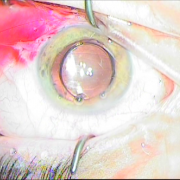

ΙΚ1 ΜΙΚΡΗ ΚΟΡΗ ΛΕΥΚΟΣ ΚΑΤΑΡΡΑΚΤΗΣ ΜΕ ΤΡΑΥΜΑΤΙΚΗ ΡΗΞΗ ΟΠ ΠΕΡΙΦΑΚΙΟΥ ΑΠΟ ΕΓΧΥΣΗ ΑΝΤΙVGEF ΠΑΡΑΓΟΝΤΑ

Μικρή κόρη λευκός

καταρράκτης με τραυματική

ρήξη οπ.περιφάκιου από

έγγχυση ANTIVGEF παράγοντα

ΕΝΘΕΣΗ ΔΙΑΣΤΟΛΕΑ ΙΡΙΔΟΣ

Ένθεση διαστολέα ίριδος

ΧΡΩΣΗ ΠΕΡΙΦΑΚΙΟΥ

Χρώση περιφάκιου

ΚΑΨΟΥΛΟΡΗΞΗ

Καψουλορήξη

ΦΑΚΟΘΡΥΨΙΑ

Φακοθρυψία

ΔΙΑΠΙΣΤΩΝΕΤΑΙ Η ΡΗΞΗ ΤΟΥ ΟΠ.ΠΕΡΙΦΑΚΙΟΥ

Διαπιστώνεται η ρήξη

του οπ. περιφάκιου

ΠΡ.ΥΑΛΟΕΙΔΕΚΤΟΜΗ

Πρ. υαλοειδεκτομή

Ένθεση φακού οπ. θαλάμου